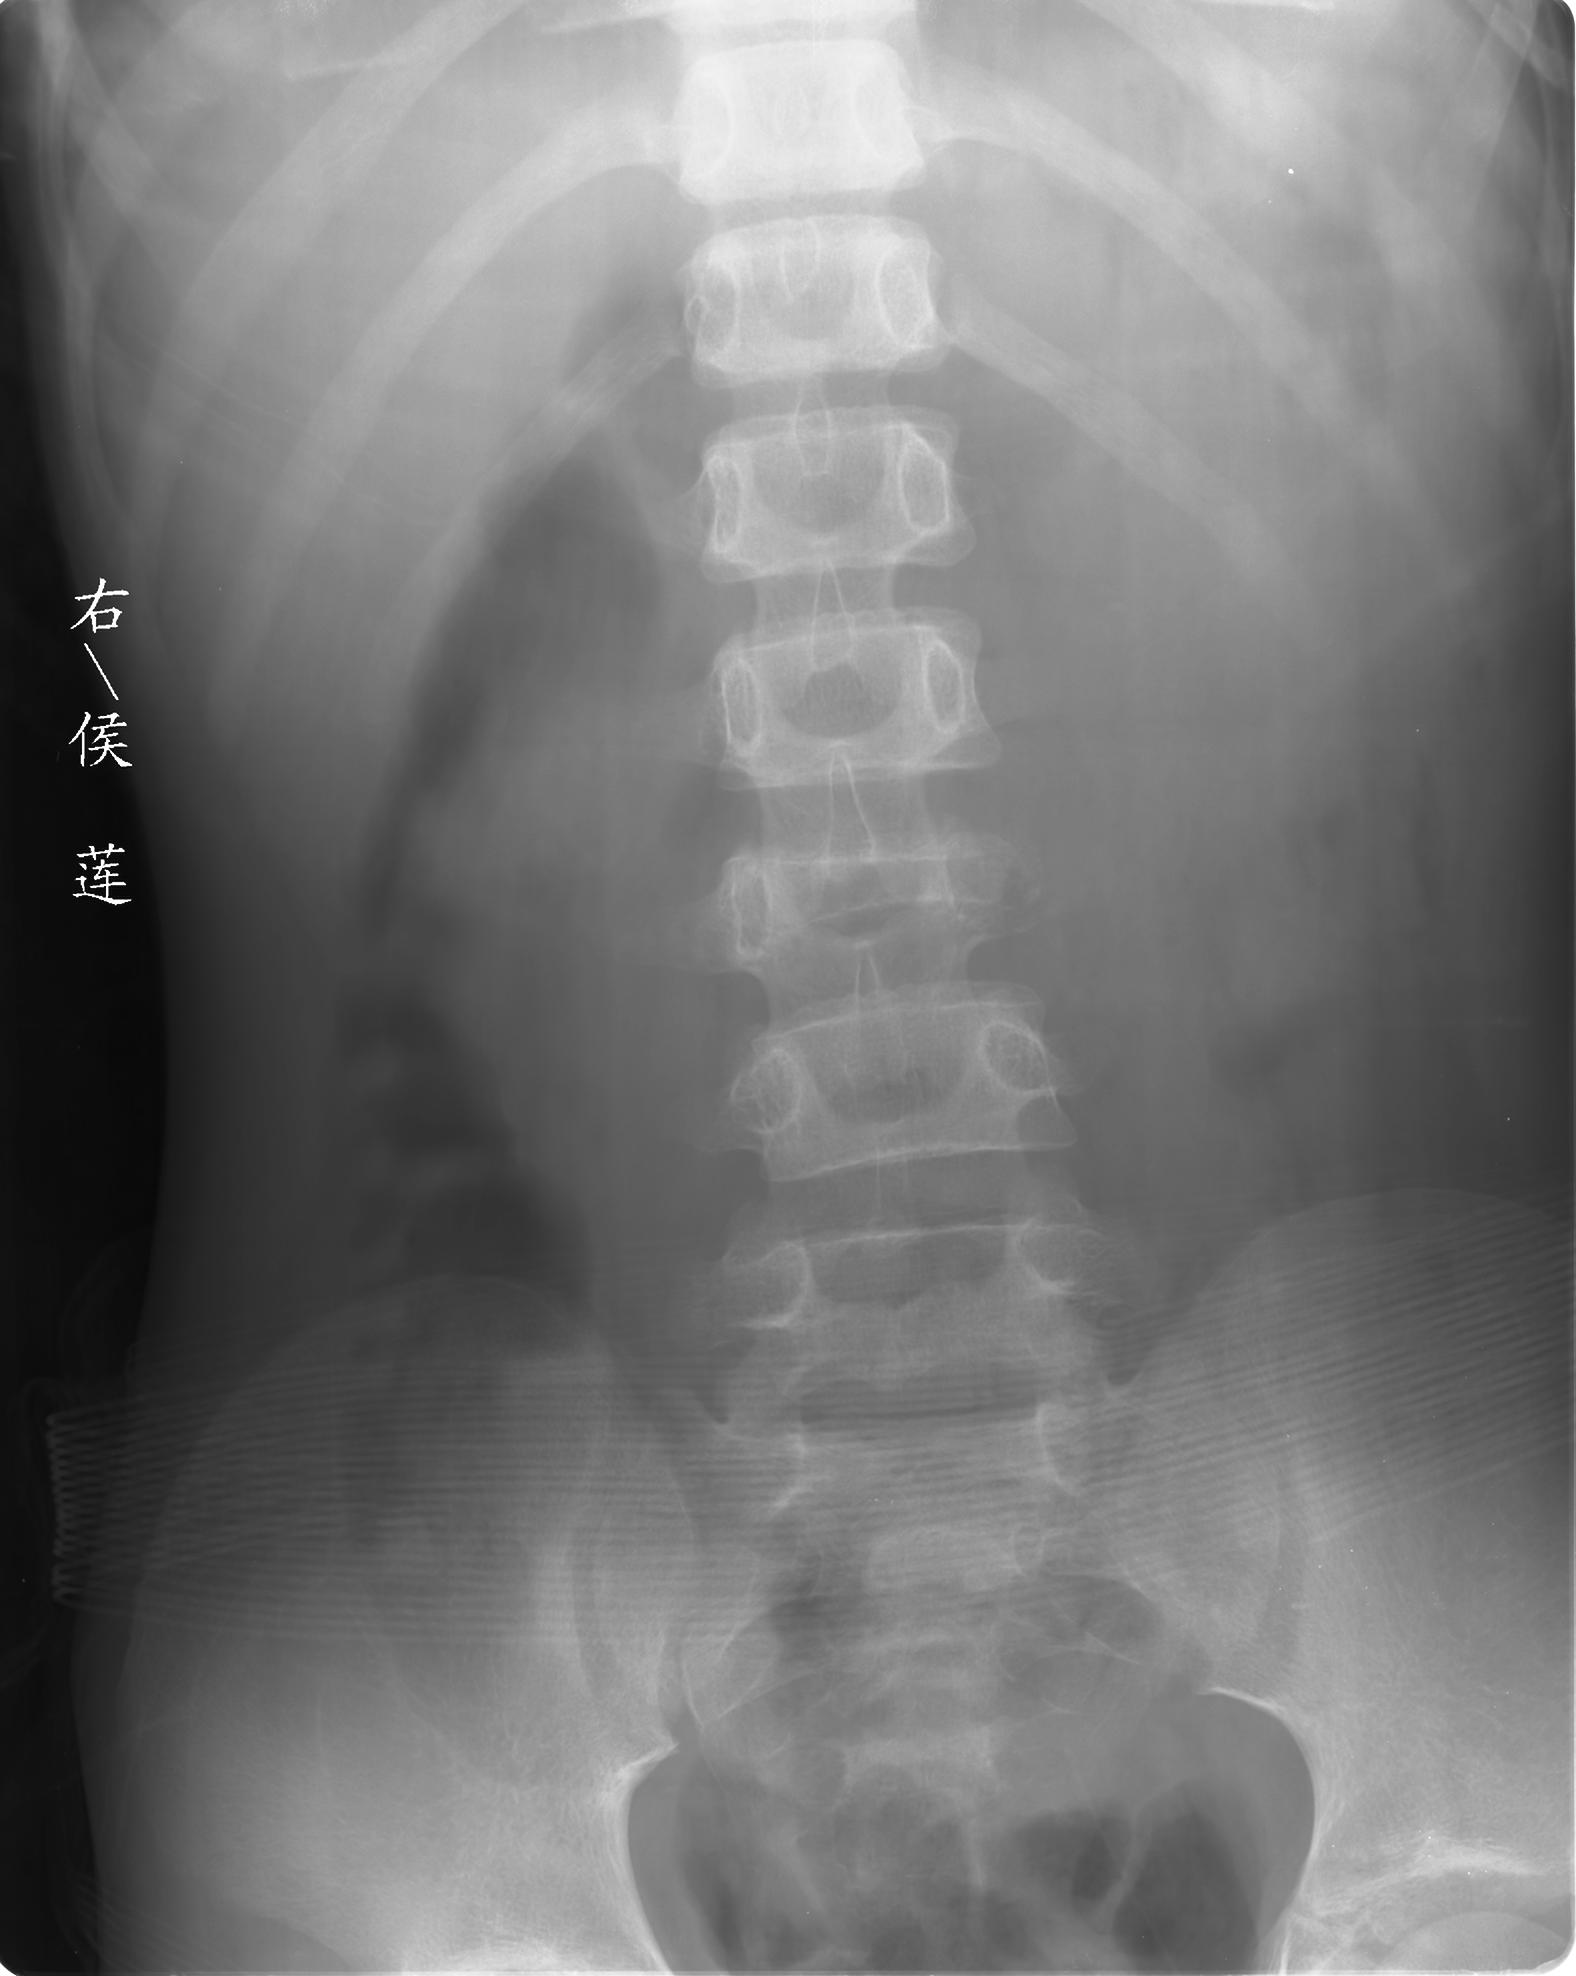

患儿女,11岁,因“腰痛,腰部活动受限10余天”入院。

10余天前,患儿无明诱因出现腰部疼痛,为持续性钝痛,以右侧为著,伴腰部活动受限,有发热,具体体温不详,无寒战、黄疸、盗汗、咳嗽,无尿频、尿急、肉眼血尿。

查:t37.8℃ bp100/60mmhg,心肺腹(-),腰部活动受限,腰椎旁有压痛,双下肢不肿,神经系统检查未见异常。

乍一看像是嗜酸性肉芽肿,但看到ct表现骨质破坏及软组织肿胀考虑结核可能性大,鉴别恶性肿瘤.

考虑l3嗜酸性肉芽肿。